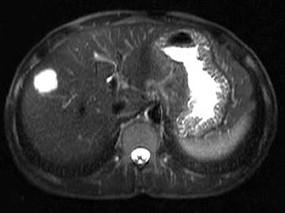

问题 男,42岁。体检B超发现肝内占位,行MRI检查见肝右叶长T1长T2异常信号。依据MRI图应诊断为 ( )

选项 A、肝脏单发转移瘤 B、未见异常 C、肝血管瘤 D、肝癌 E、肝囊肿

答案 C